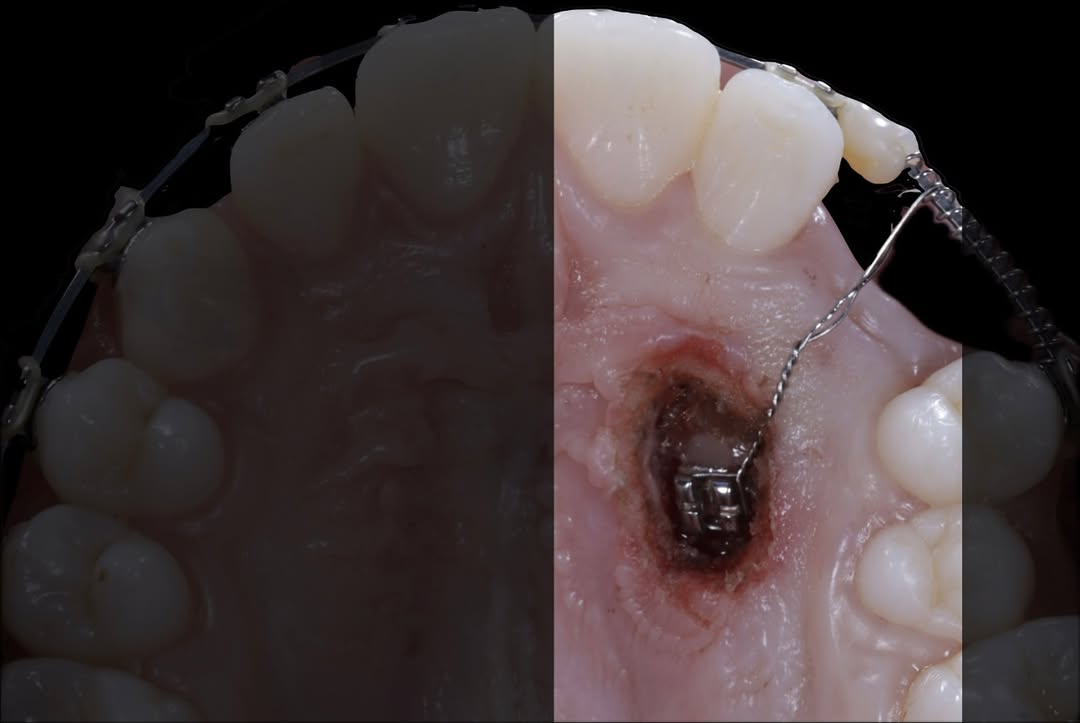

Durante esta estancia clínica tendrás la oportunidad de profundizar en las aplicaciones clínicas del láser de diodo en periodoncia, integrándolo dentro de protocolos reales de tratamiento. A lo largo de la jornada, observarás cómo se emplea el láser en procedimientos como gingivectomías, alargamientos coronarios, frenectomías y vestibuloplastias, así como su uso como coadyuvante en terapias periodontales y periimplantarias.

La formación se desarrolla en un entorno clínico real, donde el participante asiste a las intervenciones programadas y puede comprender no solo la ejecución técnica, sino también la correcta selección de casos, parámetros de configuración del láser, indicaciones, contraindicaciones y criterios clínicos que determinan su uso. Se abordarán aspectos clave como la interacción del láser con los tejidos blandos, el control del sangrado, la cicatrización y las ventajas frente a técnicas convencionales.

Esta estancia está dirigida a odontólogos de todos los niveles que deseen incorporar el láser de diodo a su práctica diaria con un enfoque seguro, predecible y basado en la evidencia clínica.